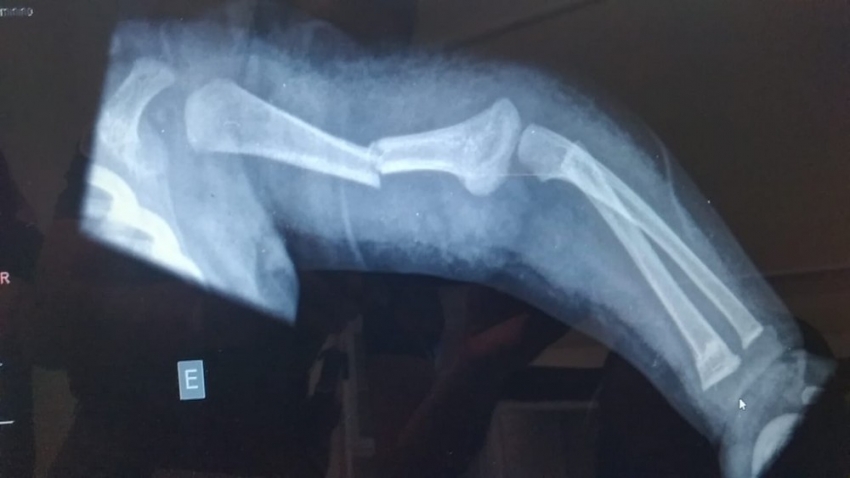

Segundo a PM, a equipe foi acionada por volta das 14h15 pelo complexo de saúde da cidade, onde a criança deu entrada com os pais, com fratura em duas partes de um dos braços.